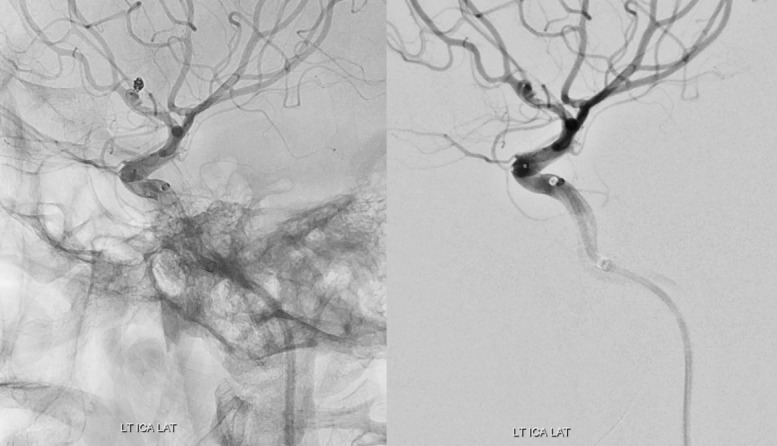

Abstract Image